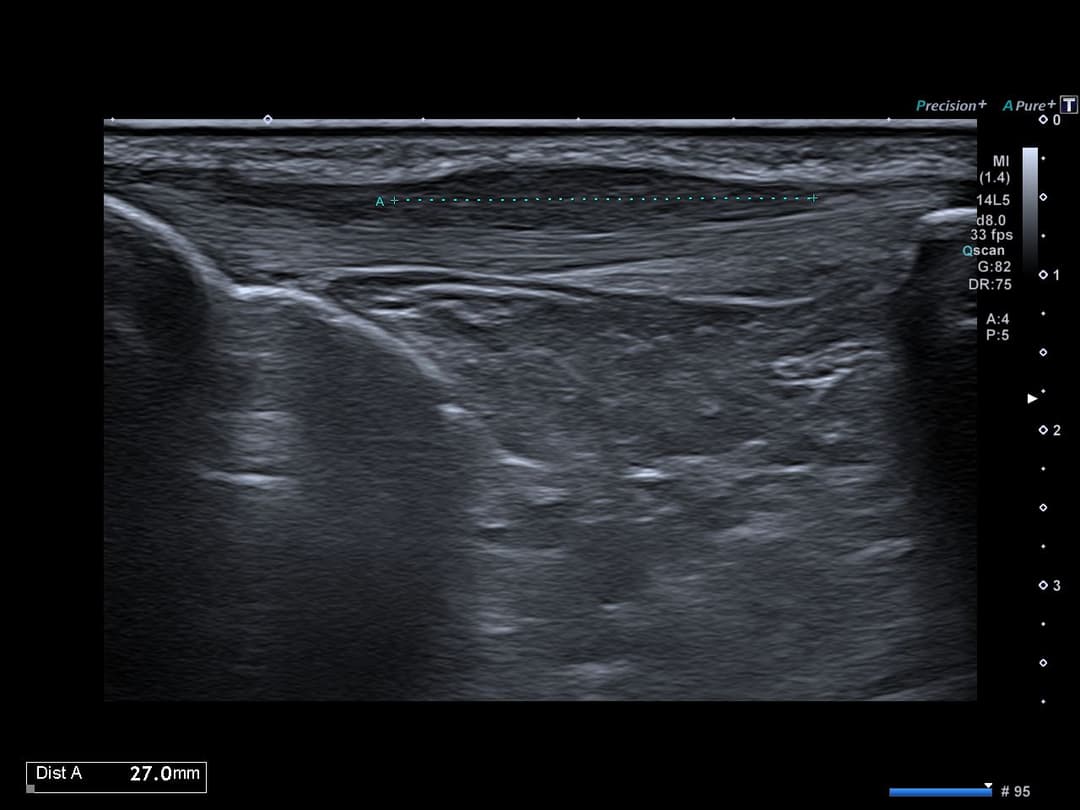

Tendinopathie patellaire corporéale superficielle

Échographie

Epaississement fusiforme avec hypo échogénicité de la portion corporéale superficielle du tendon patellaire, étendue sur 3cm de hauteur, sans fissuration intra-tendineuse notable.

Discret œdème des tissus mous cellulo-graisseux sous-cutanés adjacents.